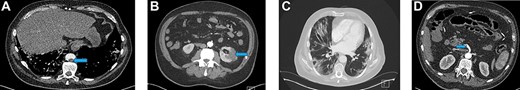

(A) Filling defect in aorta (blue arrow). (B) Left renal infarct (blue arrow). (C) CT-thorax showing pulmonary changes. (D) Thrombus in the distal SMA (blue arrow)

A repeat CT showed a SMA thrombus (Fig. 2D). Urgent angiogram and catheter-directed thrombolysis of the SMA was unsuccessful and the decision was made to operate. Exploratory laparotomy revealed a gangrenous segment of ileum necessitating resection of ~30 cm of small bowel. Re-look laparotomy at 48 hours showed no progression of ischaemia and thus anastomosis of the bowel ends was performed.